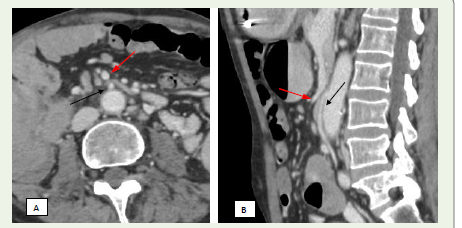

Figure 3 A-C: A 17-year-old male presenting with swelling in the left

scrotal region. (A) Axial contrast-enhanced CT image demonstrates the

characteristic “beak sign” (white solid arrow) due to narrowing of the left

renal vein. (B) Axial CT showing a reduced aortomesenteric distance (AMD)

measuring approximately 8 mm. (C) Sagittal contrast-enhanced CT reveals

a sharply decreased aortomesenteric angle (AMA) of around 48°.

CT imaging findings:

On axial CT, the “beak sign” is seen as abrupt narrowing of the

LRV at the point where it passes between the SMA and aorta, forming

an acute angle [Figure 3A] [11,12]. Sagittal reconstructions help assess the aortomesenteric angle (AMA), which normally ranges from 38°–

56°; angles under 35° are suggestive of the syndrome [13,14]. Affected

individuals also demonstrate a reduced aortomesenteric distance

(AMD), typically narrowed from the normal 10–28 mm to 2–8 mm

[1,15] [Figure 3B], [Figure 3C]. A pre- to post-compression LRV diameter ratio exceeding 2.25 has been shown to yield 91% sensitivity

and specificity for diagnosis [16]. CT may also reveal dilated gonadal

veins and pelvic varicosities, although it cannot assess blood flow

velocity or direction [11] [Figure 4A], [Figure 4B].Management: